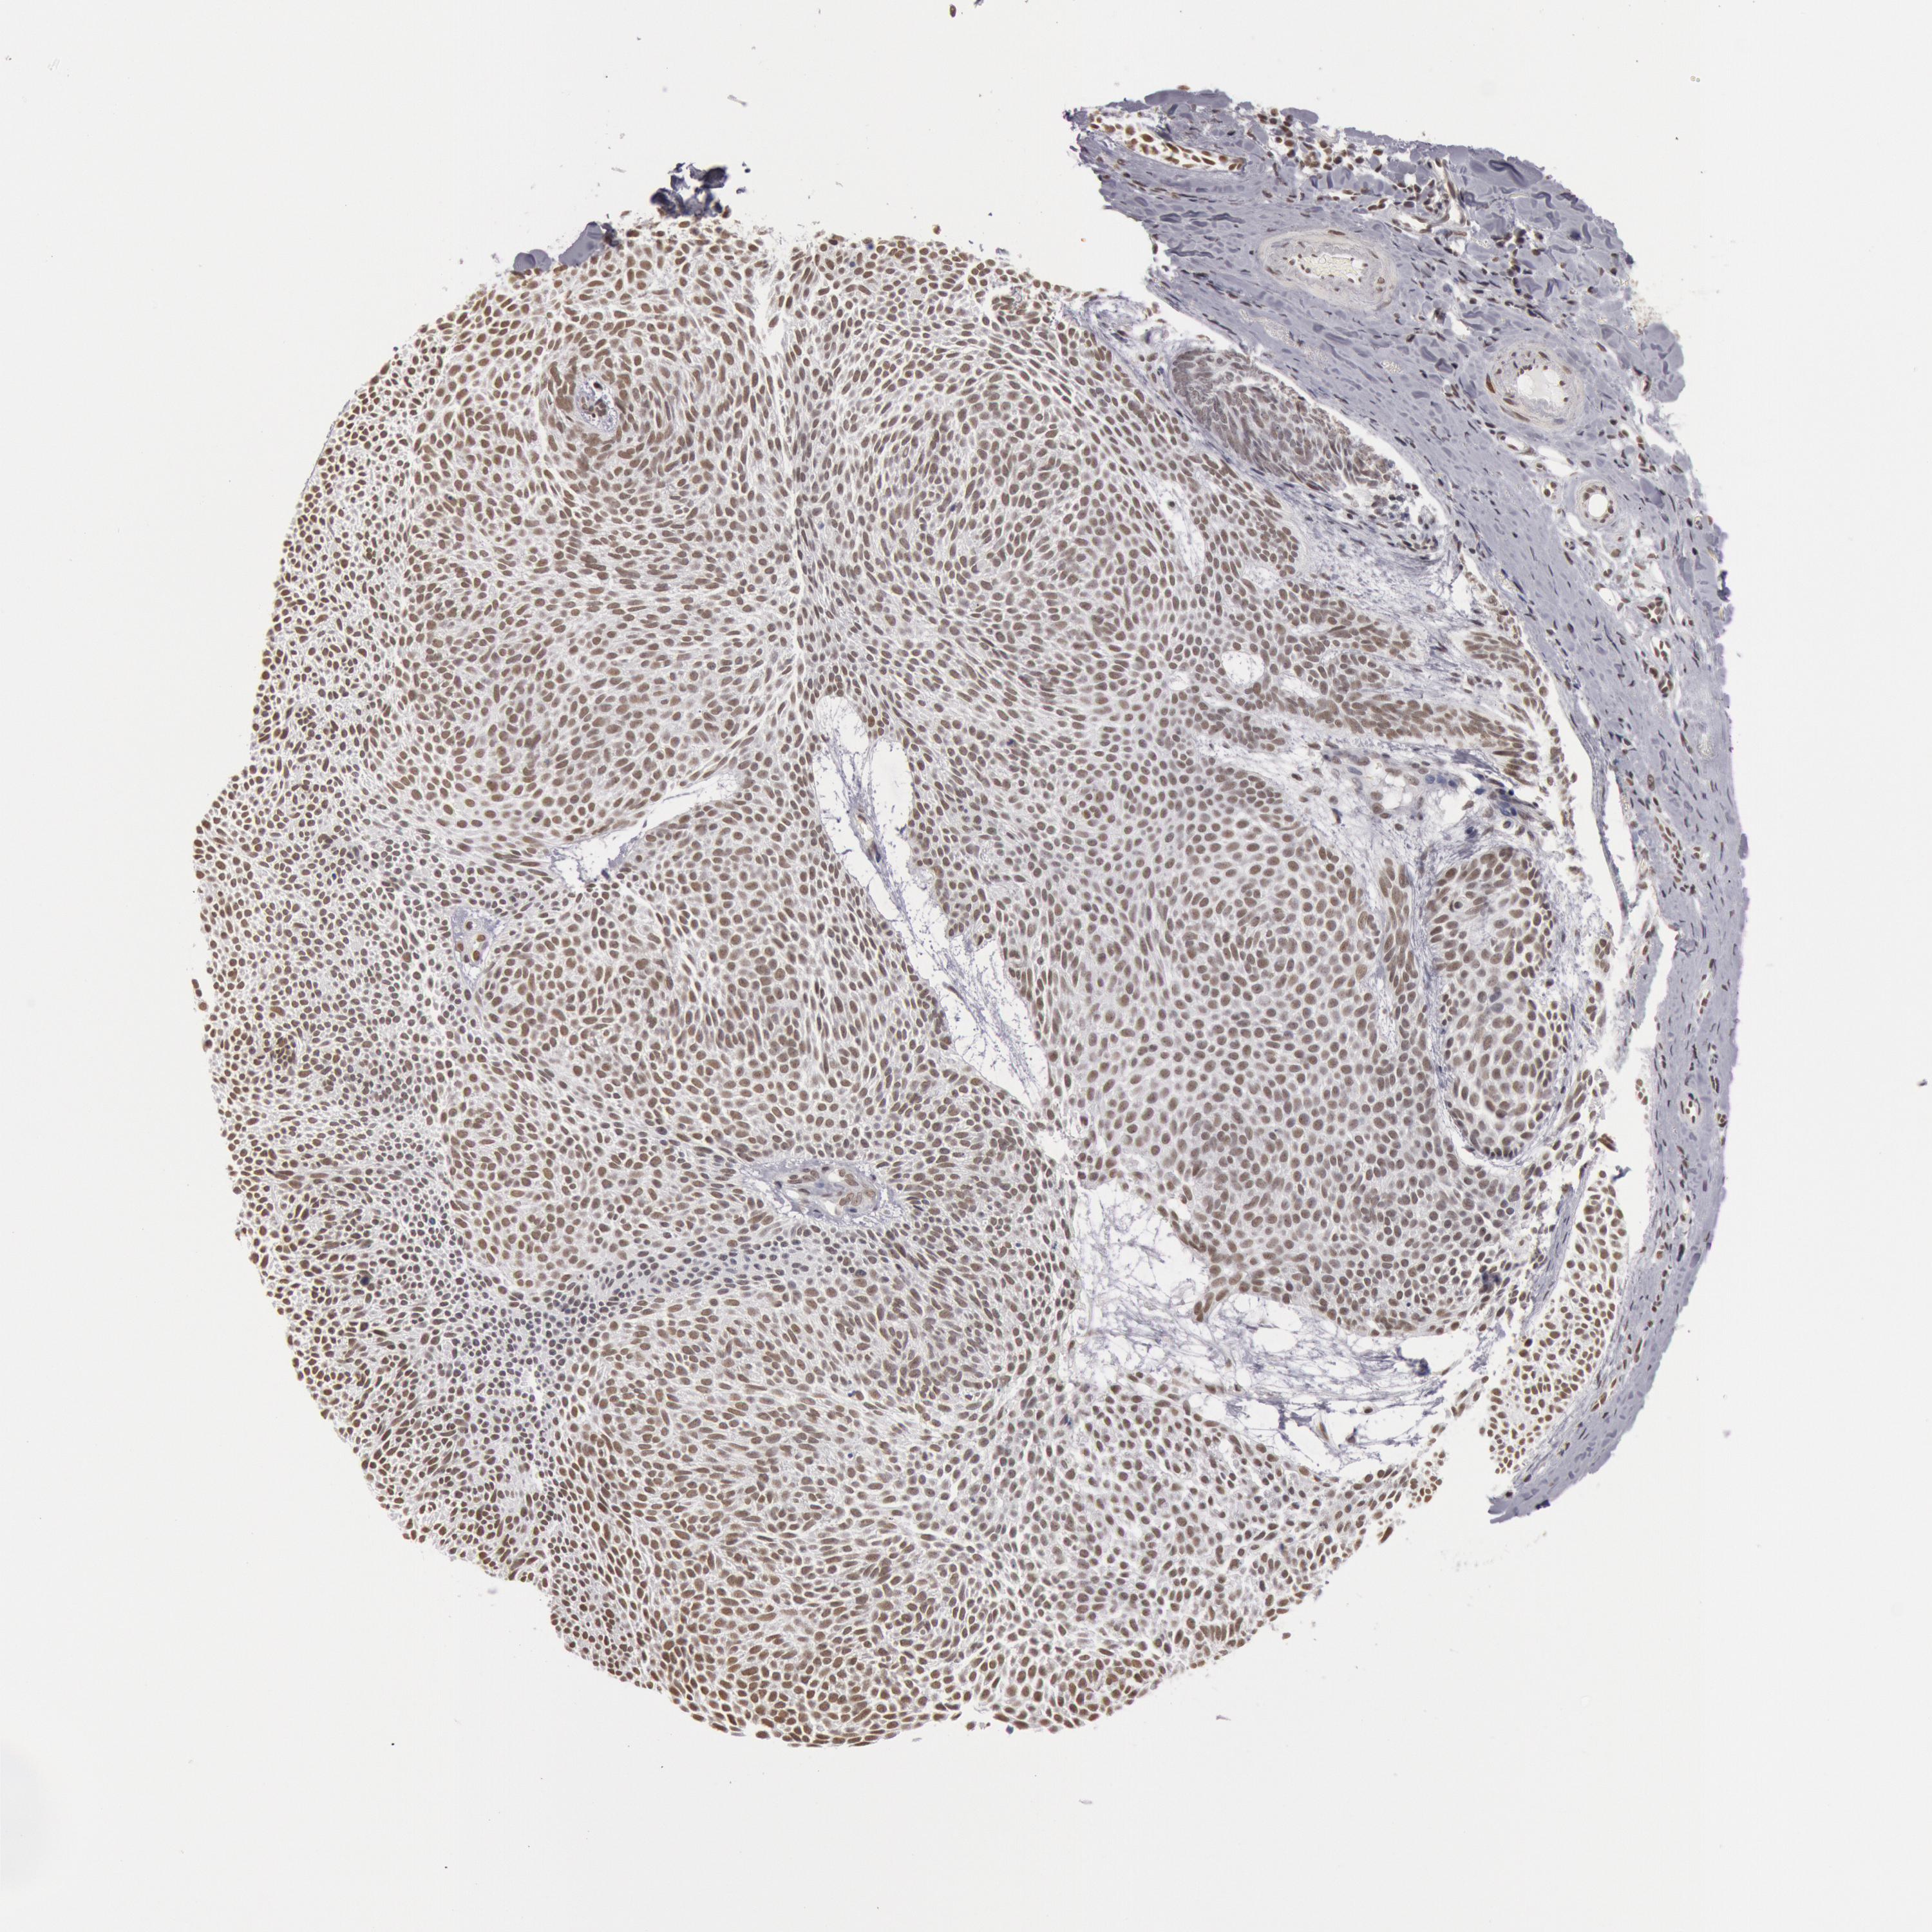

SKIN CANCER - Protein expressioni

A mouse-over function shows sample information and annotation data. Click on an image to view it in a full screen mode. Samples can be filtered based on level of antibody staining by selecting one or several of the following categories: high, medium, low and not detected. The assay and annotation is described here.

Antibody stainingi

Antibody staining in the annotated cell types in the current human tissue is reported as not detected, low, medium, or high, based on conventional immunohistochemistry profiling in selected tissues. This score is based on the combination of the staining intensity and fraction of stained cells.

Each image is clickable and will lead to virtual microscopy that enables deeper exploration of all samples and also displays staining intensity scores, fraction scores and subcellular localization as well as patient and tissue information for each sample.

Antibody HPA001221

Staining

High

Intensity

Strong

Quantity

>75%

Location

Nuclear

Squamous cell carcinoma, NOS